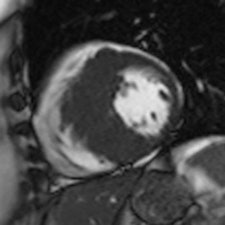

Cine MRI in short axis orientation in a patient with hypertrophic cardiomyopathy.